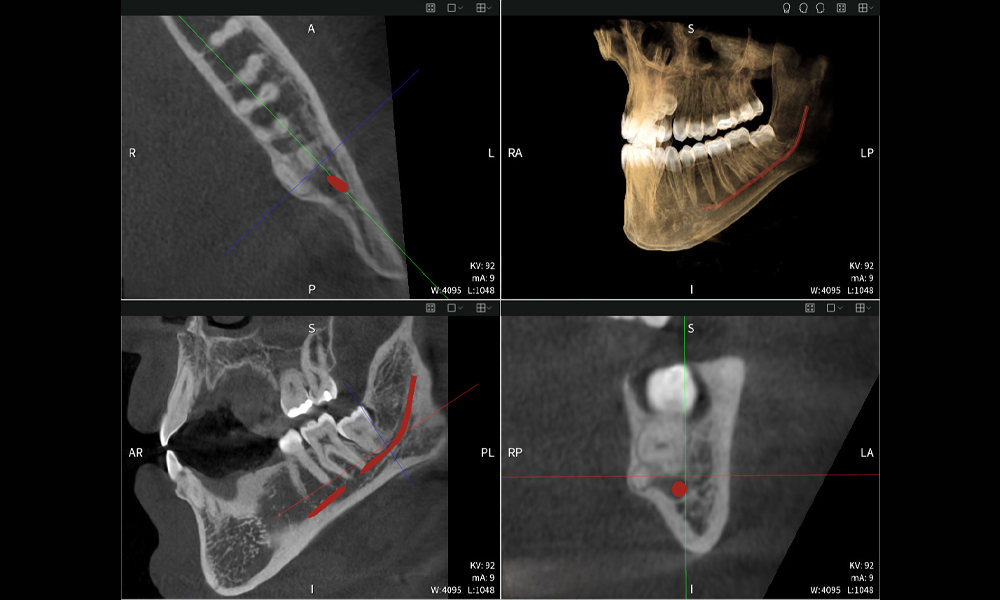

Nachstehend finden Sie einen Fall von Dr. med. dent. Oliver A. Centrella, in dem die CBCT-Aufnahmen mit Seethrough Max entscheidende Informationen zur komplexen Anatomie sowie zur kritischen Beziehung zwischen den Weisheitszähnen und dem Nervus alveolaris inferior lieferten. Bei diesem Fall besteht eine Indikation zur chirurgischen Entfernung der Weisheitszähne.

Abbildungen b–d zeigen verschiedene Ansichten einer 3D-Rekonstruktion des Unterkiefers und bieten eine umfassende Übersicht über die Anatomie des Unterkiefers, die Lage der Nerven im Verhältnis zu den Zähnen und ermöglichen die Beurteilung der Zahnsymmetrie und Ausrichtung.

Abbildung d zeigt den bereits vorbehandelten Zahn 48, dessen Krone entfernt wurde und dessen Wurzeln nahe am Nerv belassen wurden, was das hohe Risiko einer Nervenschädigung verdeutlicht.